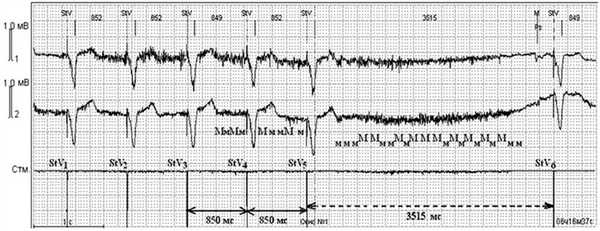

Кроме описанных выше состояний, во время операций нами были зафиксированы паузы в работе ЭКС, не связанные с ЭК. Речь идет о миопотенциальном ингибировании, которое не является истинным нарушением стимуляции, так как связано с гиперчувствительностью ЭКС к внешним воздействиям. В данной ситуации источником внешних помех явились мышцы ложа ЭКС (электрические потенциалы поперечно-полосатой мускулатуры). В левой половине рис. 7 Рисунок 7. Изолированная стимуляция желудочков (режим VVI) с базовой частотой стимуляции 70 имп/мин (850 мс). Интервал гистерезиса - не активирован. StV -желудочковый стимул ЭКС. Помехи от сокращений мышц ложа ЭКС обозначены - Мм. Пауза до 3515 мс за счет ингибирования стимуляции ЭКС. Стм. - канал ЭКС. Скорость записи 25 мм/с, усиление 1мВ=10 мм (объяснение в тексте). представлена эффективная стимуляция желудочков с базовым интервалом стимуляции, равным 850 мс (70 имп/мин). Между стимулами StV5 и StV6 пауза продолжительностью 3515 мс. Причиной асистолии явились помехи (Мм), ингибирующие работу ЭКС, воспринимаемые кардиостимулятором как желудочковые сокращения. Такие эпизоды выявлены нами при ЭКГ-мониторировании в течение предоперационного периода и во время операций только у больных с монополярной конфигурацией чувствительности ЭКС.